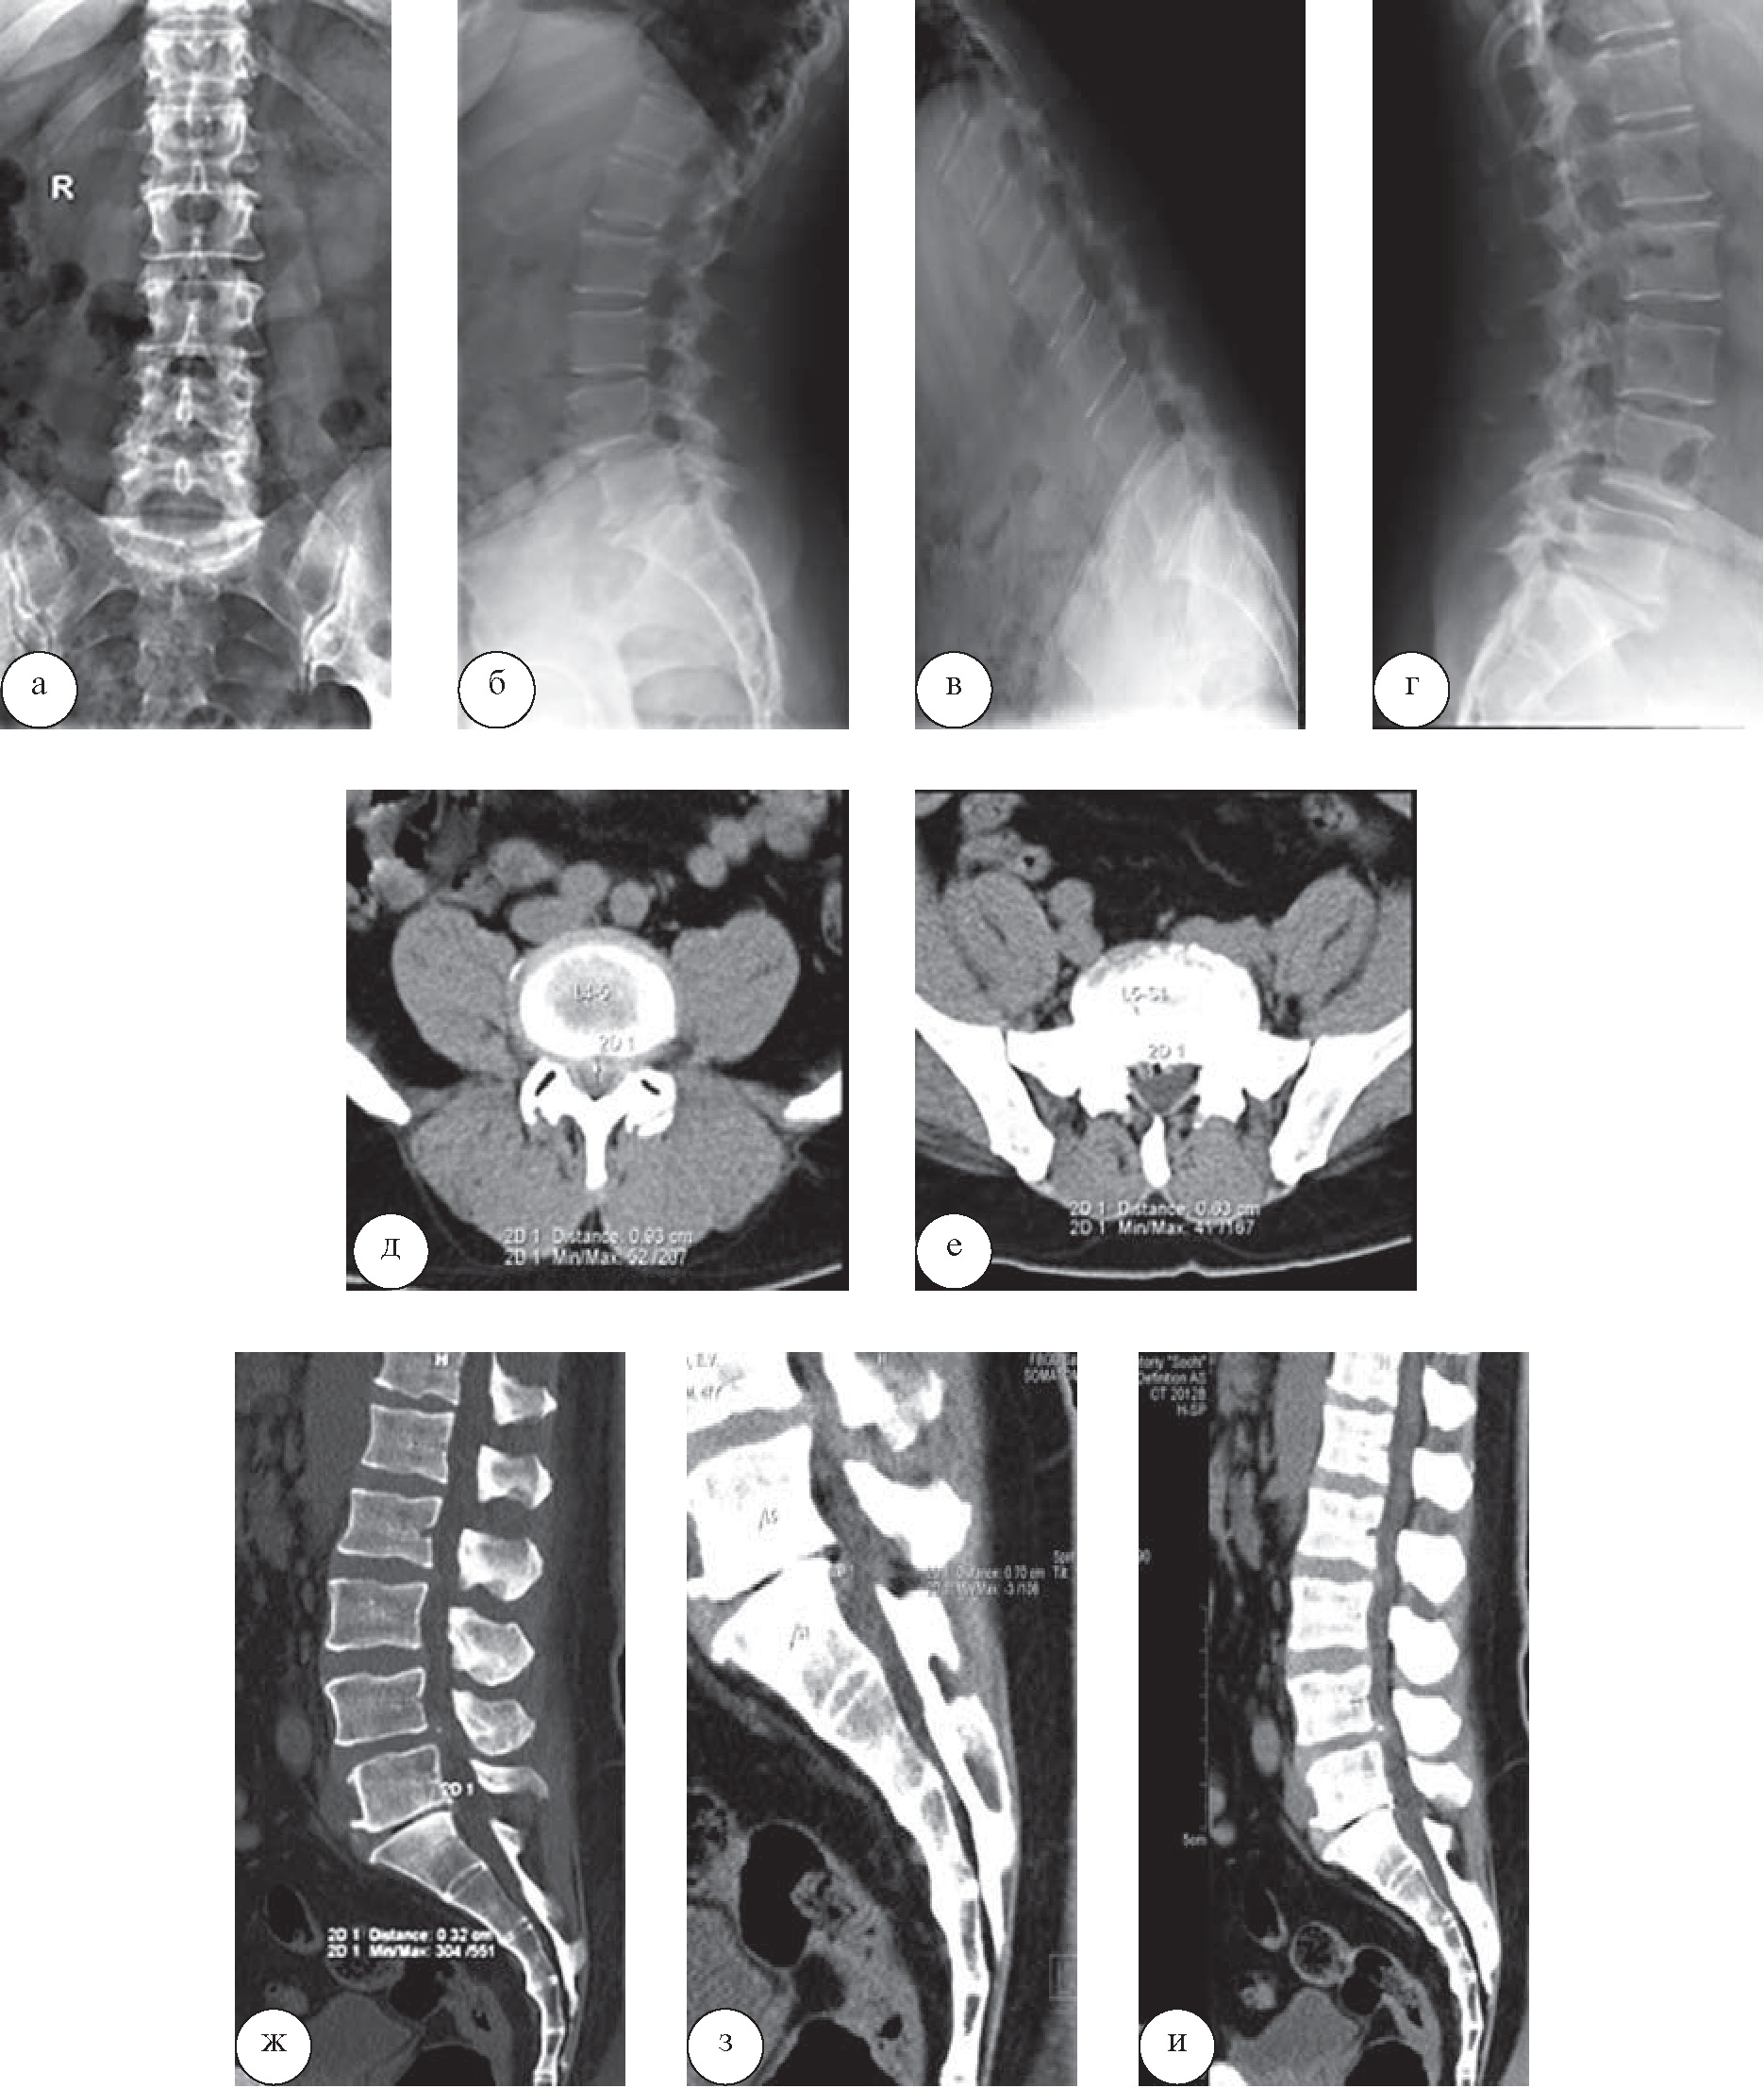

Результаты лучевого обследования, внесённые в санаторную карту пациента 47 лет, прибывшего в санаторий на лечение, были представлены лишь рентгенограммами пояснично-крестцового отдела (рис. 7, а–г). В связи с выраженным болевым синдромом пациенту была выполнена КТ (рис. 7, д–и), при которой диагностированы грыжа межпозвонкового диска L4–5, выступающая до 9 мм и субтотально суживающая просвет позвоночного канала и корешковые отверстия, а также выступающая до 7 мм сублигаментарная грыжа диска L5–S1, разнонаправленные дегенеративные спондилолистезы двух соседних позвонков.

Рис. 7. Пациент Р., 47 лет. При рентенографии пояснично-крестцового отдела позвоночника в прямой и боковой проекциях (а, б) и выполнении функциональных проб (сгибание (в) и разгибание (г)) определяются проявления остеохондроза поясничного отдела позвоночника, спондилоартроза, переднего дегенеративного спондилолистеза позвонка L4 1 степени. На компьютерных томограммах в аксиальной (д, е) и сагиттальной (ж–и) плоскостях выявляются задняя грыжа диска L2–3, выступающая до 5 мм, задняя диффузная грыжа межпозвонкового диска L4–5, выступающая до 9 мм и субтотально суживающая просвет позвоночного канала и корешковые отверстия; задняя медиальная частично обызвествившаяся грыжа межпозвонкового диска L5–S1, максимально выступающая до 7 мм на уровне верхней трети тела S1 и распространяющаяся вдоль задней продольной связки. Позвоночный канал на уровне L4–5 сужен грыжей диска и имеет размеры 4×9 мм. Корешковые отверстия L5–S1 сужены за счет остеофитов. Имеются выраженные проявления остеоартроза дугоотростчатых суставов L4–S1. Отмечается передний дегенеративный спондилолистез позвонка L4 до 4 мм, задний дегенеративный спондилолистез позвонка L5 до 3 мм

Больному проведена консультация нейрохирурга, показаний к срочному хирургическому вмешательству и отмене санаторного лечения выявлено не было. Из программы лечения исключены механотерапия и теплотерапия на поясничную область, назначены аппаратная физиотерапия и медикаментозная терапия.